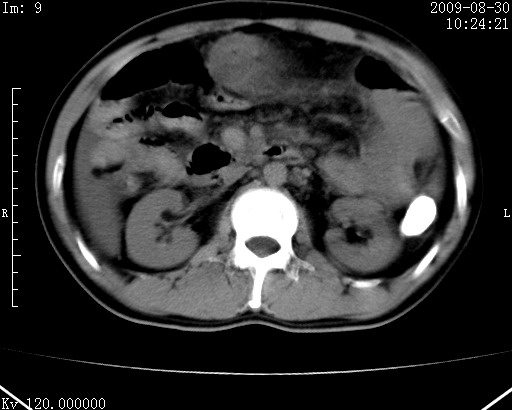

患者唐某,男31岁,已婚,本地务农。

自述入院前两天一次进食较多冷饮之后,出现阵发性上腹部疼痛,次日加剧伴恶心、呕吐,呕吐后症状稍减轻。食欲差。大便每天1-2次,量少,暗红色水样。小便赤。无畏寒、发热、咳嗽等呼吸道症状。无高血压及胃病史。

检查:体温、血压及脉搏正常.皮肤无黄染,浅表无淋巴结肿大。左腹肌紧张,左上腹有压痛,无反跳痛,可触及包块。

生化:钾、钠、氯、钙、ph正常,总胆红素和直接胆红素稍高,空腹血糖稍高。

尿淀粉酶:1256 u/l(正常60-401)。

血常规:wbc 22.4x109/l gr88% ly9.6%其余基本正常。

胃镜:急性胃炎。立位腹平片:未见异常。

下面是ct平扫,降结肠内是对比剂。

术前影像诊断:上段空肠急性缺血性坏死并腹水。建议手术治疗。

术中见上段空肠约70cm长范围坏死,从屈氏韧带远端约10cm处开始。坏死肠管肿胀变形变色,管壁明显环形增厚,部分聚成大肿块,无扭转和套叠。肠系膜上动脉分支内广泛泥沙状血栓。肠切除。

临床诊断:肠系膜上动脉梗塞并急性肠坏死。

开始时我们科也有人认为是套叠,最后统一意见,不考虑肠套。我们看到的“靶征”,“晕圈征”,“双圈征”实际上只是单根肠管的横断面。坏死肿胀后肠壁各层的密度不一样。

左侧腹小肠腔管壁明显增厚,部分内示靶征,走行异常,部分肠系膜绳样改变,肝包膜下及肠间较多液体密度,然梗阻近端肠腔积气不明显。

考虑;肠扭曲伴肠坏死。

有结果了,回顾分析,套叠只会在局部出现同心圆征,不会很长一段肠管都有,还是水肿坏死。